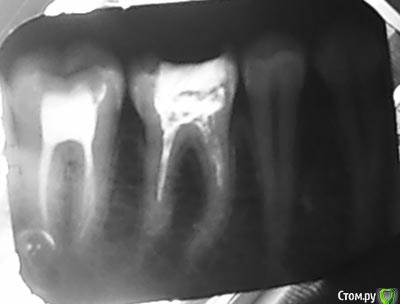

SAnet Опубликовано 31 мая, 2015 Автор Поделиться Опубликовано 31 мая, 2015 Вроде как вот) Ссылка на комментарий

parallax Опубликовано 31 мая, 2015 Поделиться Опубликовано 31 мая, 2015 А который из них Вас гнетёт? Оба моляра не айс. Ссылка на комментарий

St. Опубликовано 31 мая, 2015 Поделиться Опубликовано 31 мая, 2015 Может стоит подумать о смене доктора?. Каналы не очень.. Ссылка на комментарий

SAnet Опубликовано 31 мая, 2015 Автор Поделиться Опубликовано 31 мая, 2015 Я пробовал. Сказали 6 как есть... дальше не могут пройти канальчики) брет? и вообще реакция на холод сильная есть) боли) потом резко проходит Ссылка на комментарий